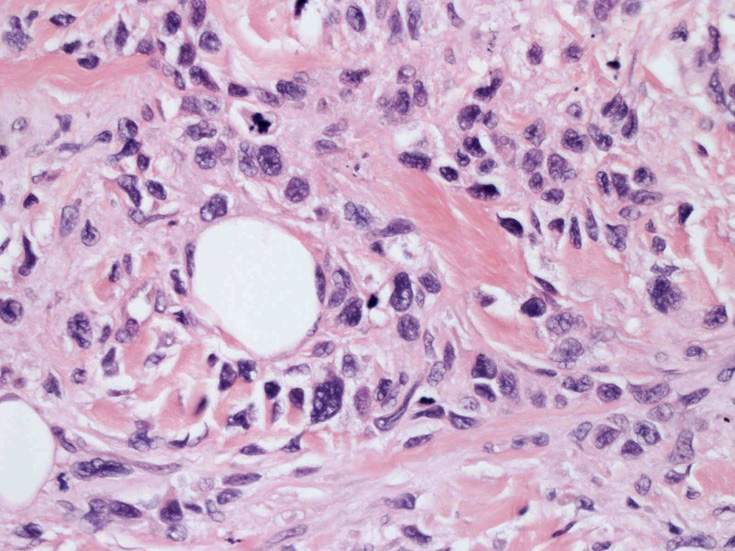

皮膚生検組織。細胞浸潤が表皮, 表皮真皮境界部, 真皮, 皮下組織にびまん性に認められる。血管中心性に結節様の分布があるように見える。

皮膚に異型細胞の浸潤がみられる。異型細胞は表皮内に浸潤するほか、表皮真皮境界部, 真皮, 皮下脂肪組織にもびまん, 結節様の浸潤所見を示す。血管周囲に浸潤、集蔟する所見も多く見られる。 増殖浸潤細胞の核には類円形や腎臓形, またはへこみ, 切れ込み, 溝などを有する多型な核が認められる。クロマチンは粗でvesicularな核が多い。核小体の明らかな核もある。好エオジン性の核内封入体様構造も少数に見られた。mitosisは容易に認められる。hyperchromaticな多型核, bizzarreな細胞が高頻度に認められ異型度は高いと考えられる。細胞質は境界不明瞭, 淡明または泡沫様の 好エオジン性胞体である。